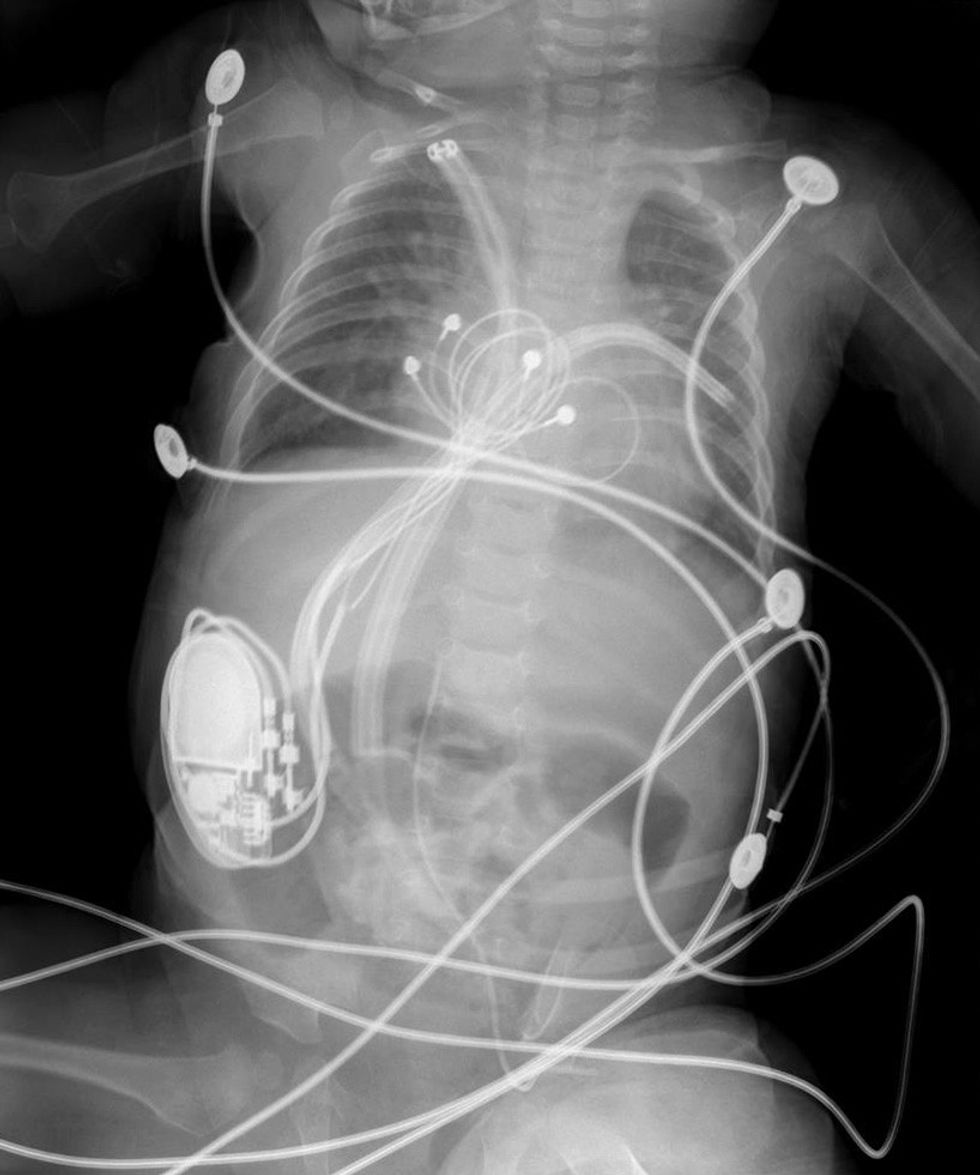

Në spitalin "Zhan Mitrev" në Klinikën për Kardiokirurgji për herë të parë është vendosur stimulues kardiak tek një foshnje 5 mujore.

Foshnja e cila peshon 4.5 kilogram, ka sindromin "Down", ndërsa me sukses po shërohet nga operacioni në defektin septal atrioventikular dhe pritet të dalë nga spitali.

Stimuluesi (pejsmejker) i cili për herë të parë është vendosur tek një fëmijë i moshës së tillë, është vendosur për shkak të çrregullimit të ritmit të zemrës. "Pejsmejkeri" është stimulues i përhershëm epikardial i dyfishtë.

Ekipi i spitalit "Zhan Mitrev" i udhëhequr nga mjeku Vlladimir Çadikovski dhe mjeku Zhan Mitrev, në bashkëpunim me profesorin Nikolla Gjorgov e kanë vendosur stimuluesin kardiak tek foshnja.